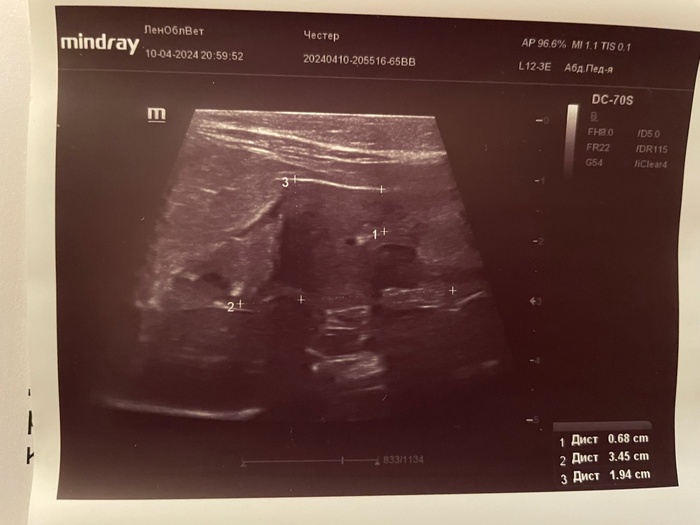

Также были назначены анализы: на электролиты, биохимия мочи, узи мочеполовой системы. Ниже в карусели прикладываю все результаты: